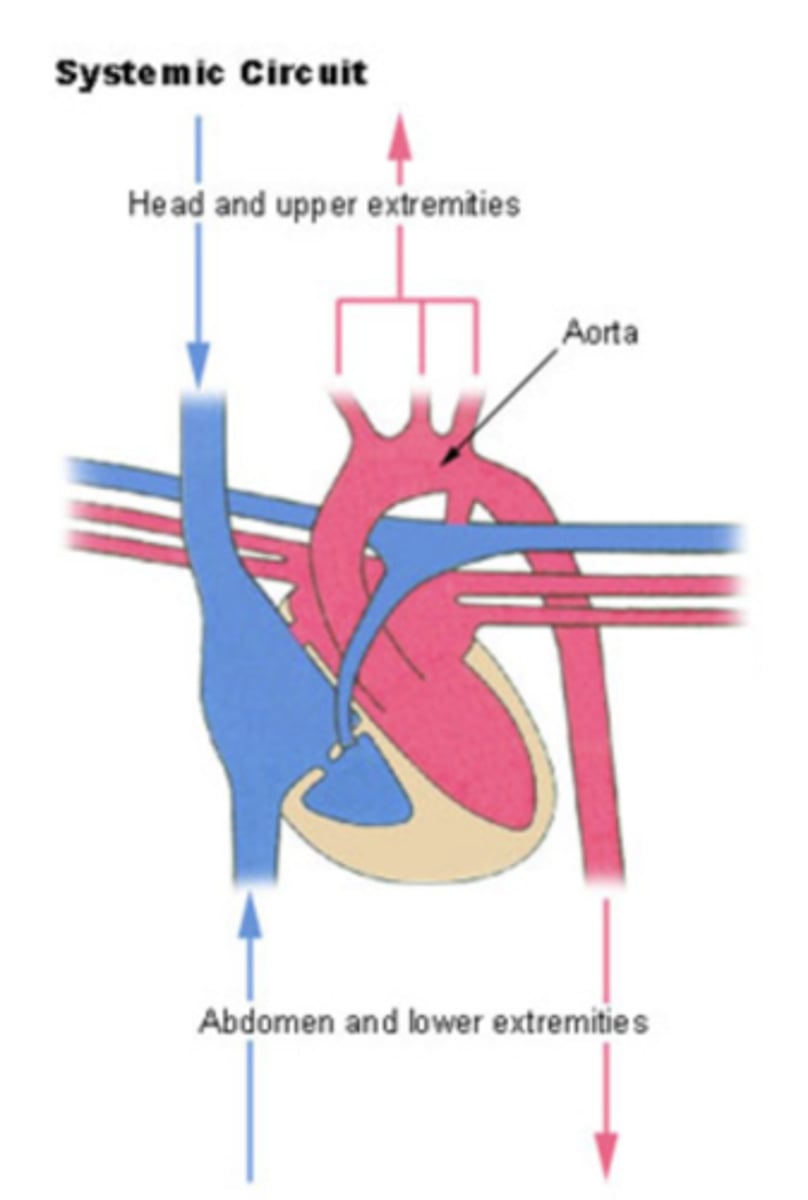

SYSTEMIC CIRCULATION

flow of blood from body tissue to the heart and then from the heart back to body tissues

It carries oxygen and nutrients to the cells and picks up carbon dioxide and waste products

Describe in detail systemic circulation

From the left ventricle, oxygenated blood,

through the arteries,

to the capillaries in the tissues of the body.

From the tissue capillaries, the deoxygenated blood

returns through a system of veins to the right atrium of the heart. (superior and inferior cava veins)

from where is the right atrium receiving the blood?

From the whole body

Right ventricle pumps blood to?

pulmonary artery

from where receives blood the left atrium?

pulmonary veins

Where pumps blood the left ventricle?

into the aorta